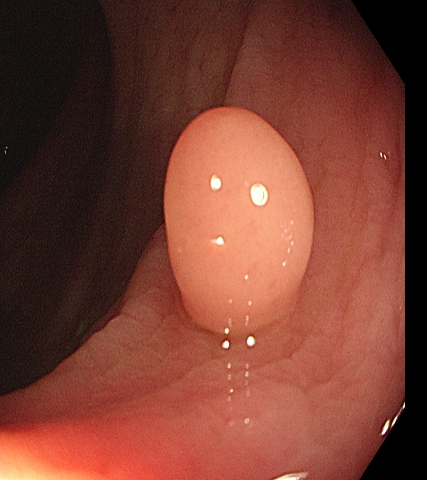

操作过程中应夹住息肉头端,适当上提(可避免损伤肌层),与肠壁保持适当距离,当息肉蒂部出现发白时,停止电凝,钳除病变。应注意是,切除息肉不易过大,否则会造成通电时间延长,增加全层损伤的风险(图1)。

图1 热活检钳除术示意图,A 钳除前,B 钳除后创面。C-D:热活检钳除术注意事项,息肉体积过大,增加电凝时间,造成透壁性损伤。